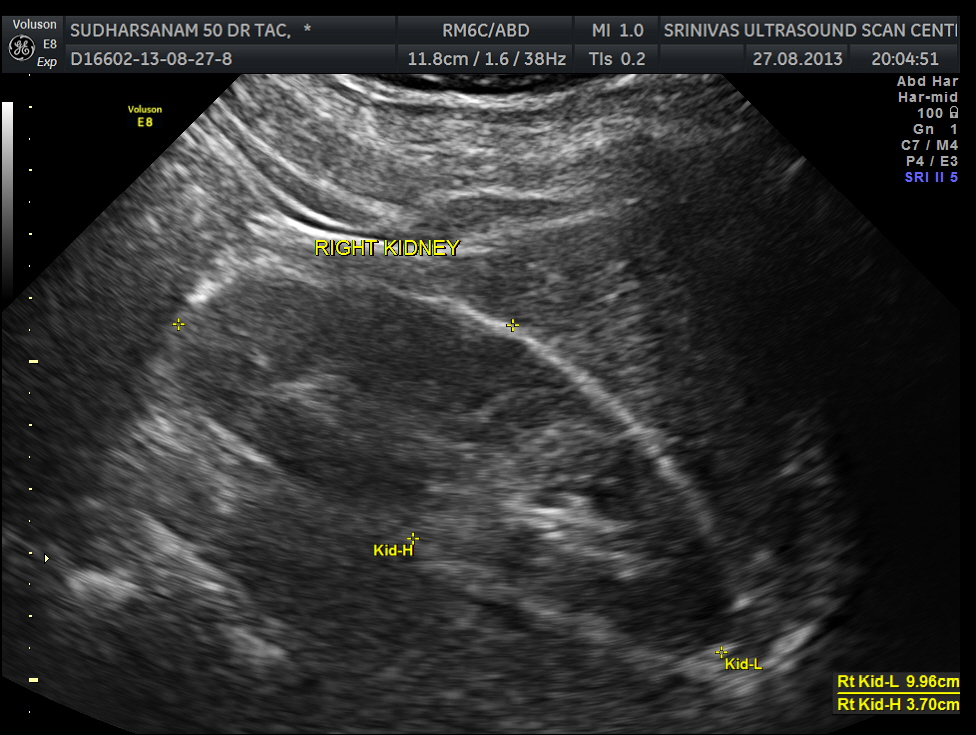

images of the kidney are given below.

He had an essentially normal appearance of the upper abdominal organs . His kidneys also appeared to be normal.